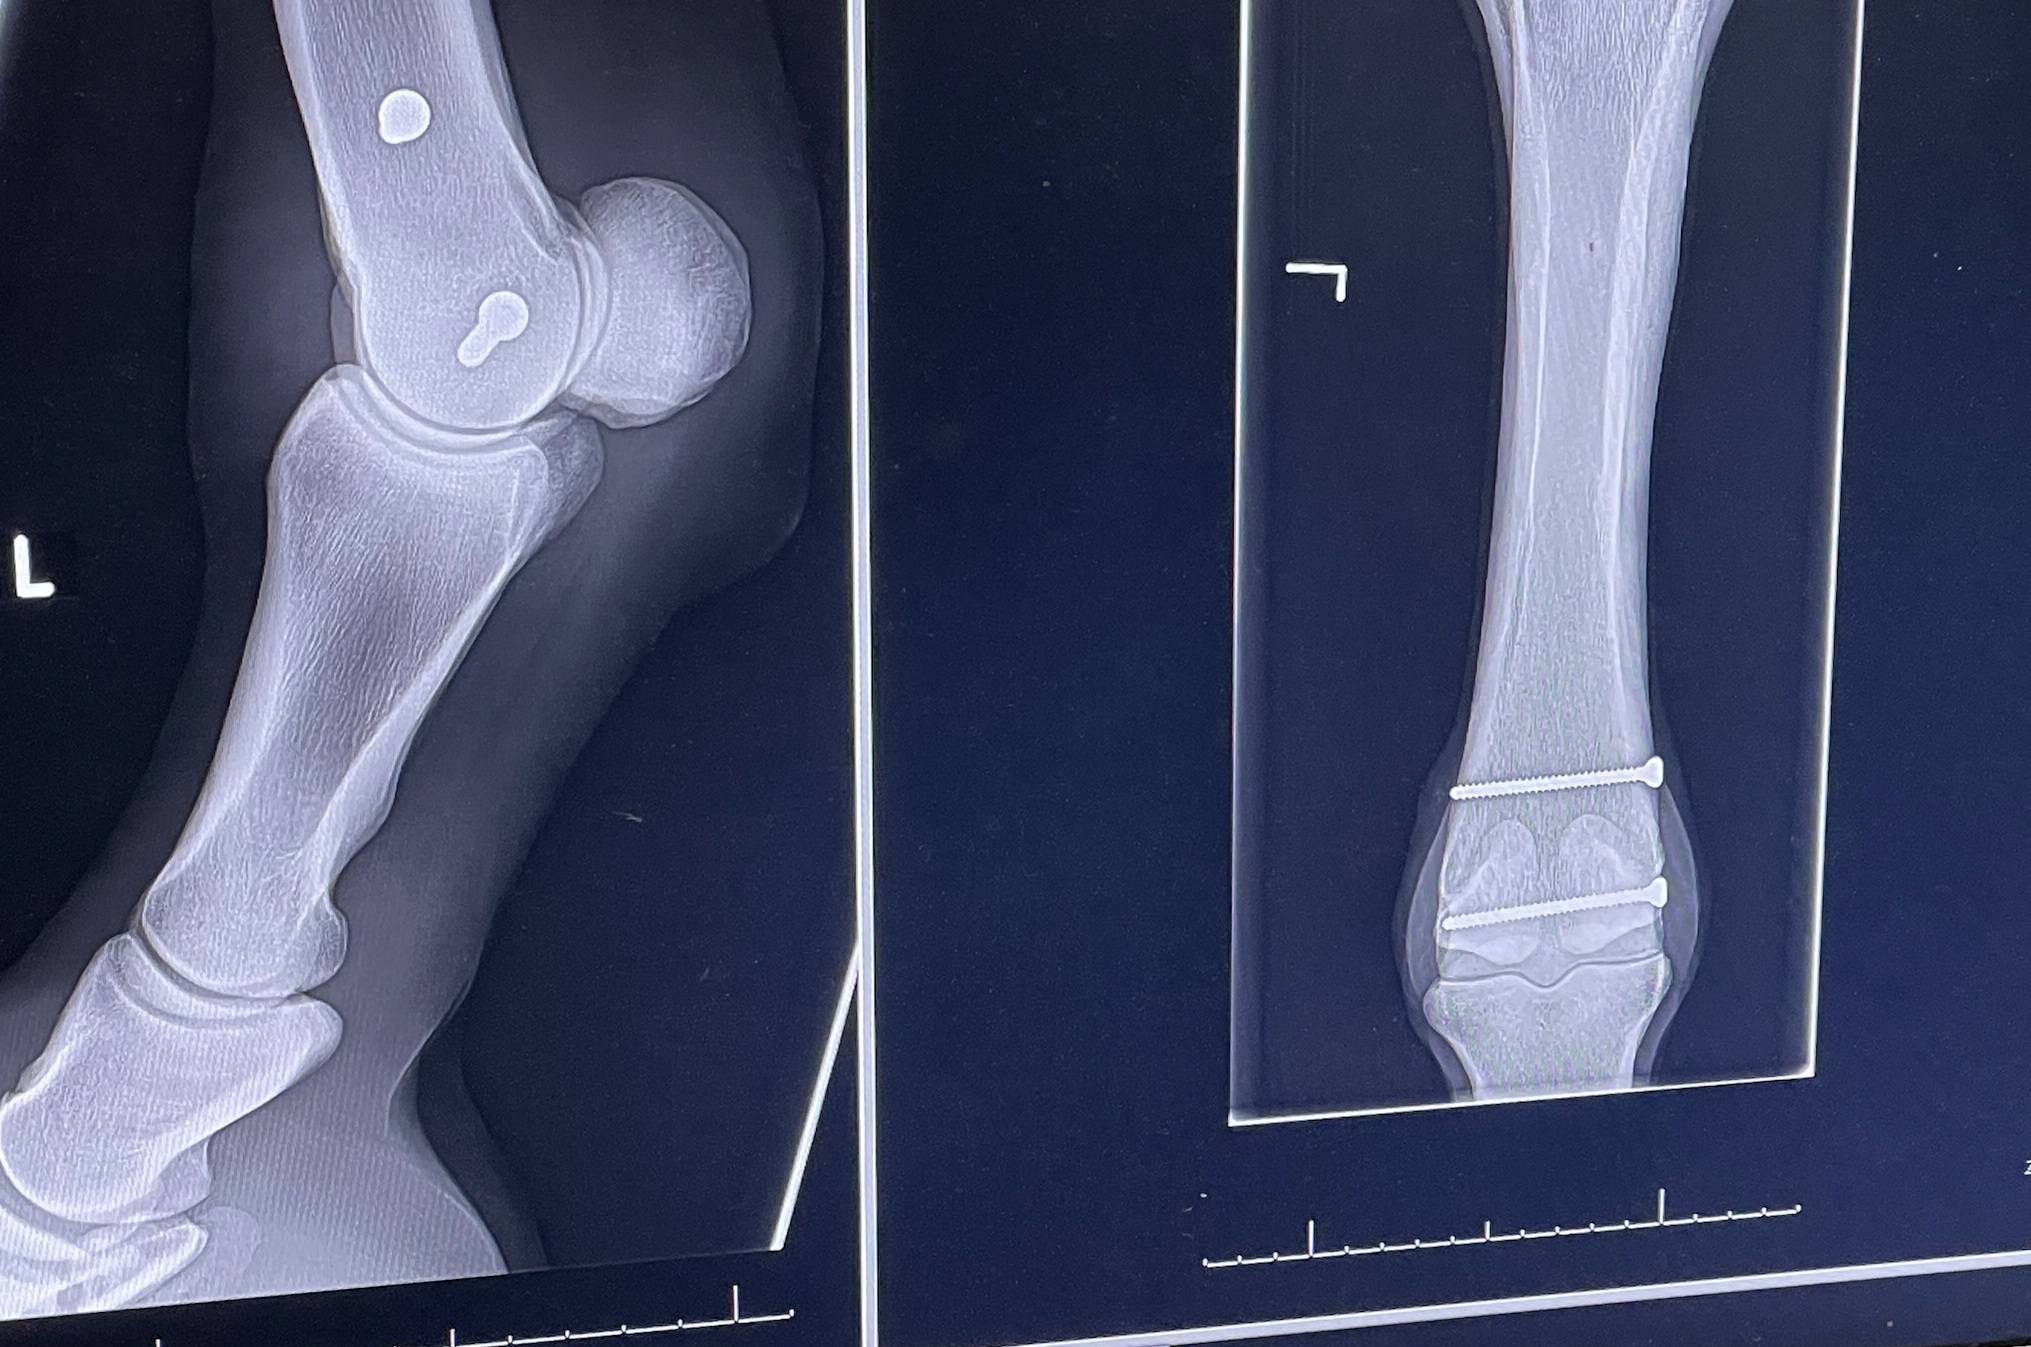

So sieht das nun aus bei Vessillo, linker Fesselkopf, ganz unten im Röhrbein sind zwei Schrauben.